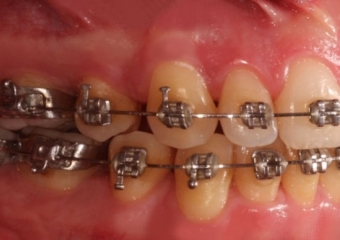

Mordida inicial